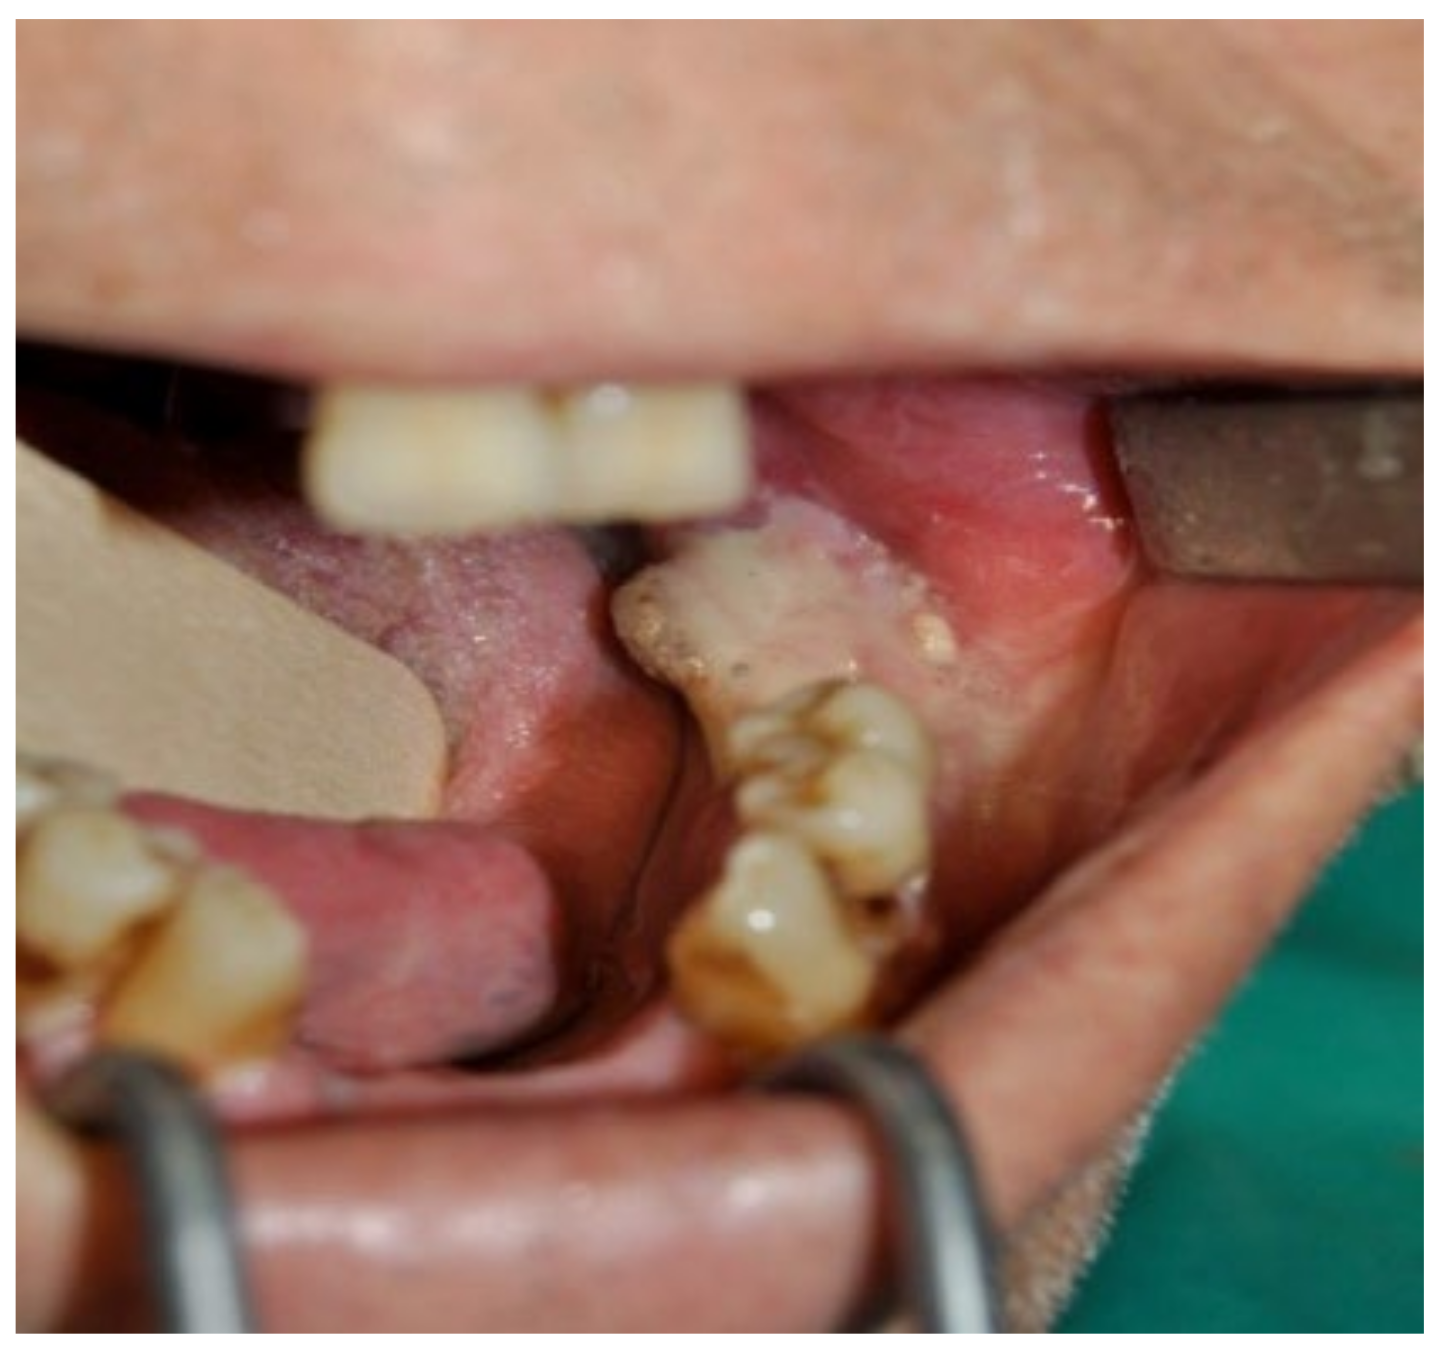

3.5. Clinical Case 5

3.6. Clinical Case 6